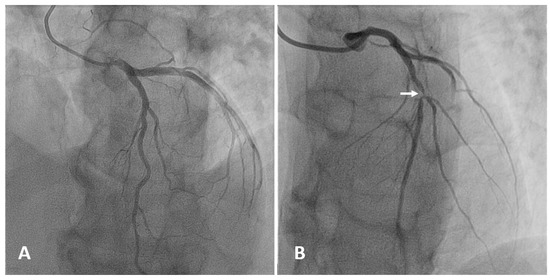

The intravenous administration of iodine contrast media allows the assessment of coronary stenosis and several adverse coronary plaque characteristics, such as spotty calcification, positive remodeling, and low-attenuation non-calcified plaques which identify a large necrotic core [68,69]. (Figure 2 and Figure 3). However, smaller components such as microcalcifications and TCFA cannot be detected because their dimension is ten times lower than the spatial resolution of CTCA (about 500 microns) [70].

Figure 2.

Right coronary artery (RCA) studied with CTCA (A) and with coronary angiography (B) in the same patient. Both examinations show a narrowing of the arterial lumen in the proximal RCA segment (arrows), indicating the presence of an atherosclerotic plaque. CTCA imaging shows a low-attenuation non-calcified plaque which identifies a lipid or necrotic core. Calcifications are hyperdense on CTCA, while not visible on coronary angiography.

Figure 3.

(A) CTCA showing the left main (LM) and left anterior descending (LAD) coronary arteries of a patient who underwent coronary angioplasty (PTCA) and stent positioning in the LM. A non-calcified low density soft plaque (white arrow) is shown between calcific plaques; the hypodense spot (dashed white arrow) within the stent may indicate initial intrastent restenosis. Calcification of the aortic valve leaflets. (B) CTCA of the same patient reformatted in the plane of the aortic valve shows calcification of the aortic leaflets. RVOT: right ventricle outflow tract; LA: left atrium; PA: pulmonary artery.